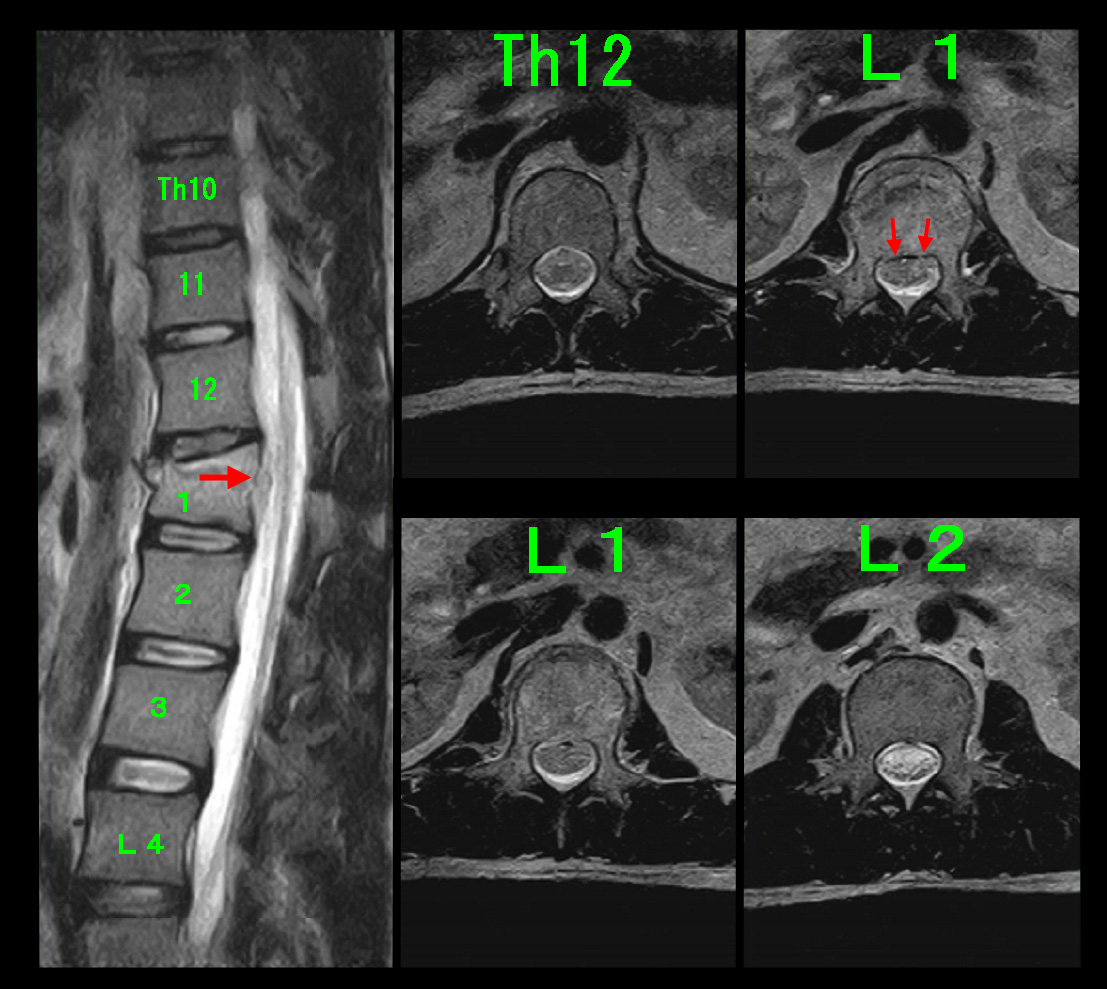

82才男 MR1.jpg

腰椎MRI検査ではL45で重度の脊髄の圧迫(赤矢印)が確認されます。第12胸椎圧迫骨折に起因するオレンジ丸領域の腰痛が軽減して、元々あった腰椎の老化による脊髄圧迫による腰痛と右足指の坐骨神経痛が症状を出したのだと判断します。そこでL45高位で足指の痛みある左側の神経根ブロックを施行しました。

44才男 MR.jpg

その時のMRI画像となりますが、圧迫骨折を発症した第1腰椎の右上の水平断では脊髄の軽度~中等度の圧迫の所見が確認できます(赤矢印)。第12胸椎(Th12)と第2腰椎(L2)高位での脊髄は円形または楕円形の形態です。第1腰椎での脊髄の圧迫が右第1足指の違和感の原因となってもおかしくはないと考えます。令和5年には腰椎MRI検査は行っていませんが、松飾りで受傷したKさんのように腰椎の下位レベルで加齢による椎間板ヘルニアが起きていて、第1腰椎の変形と椎間板ヘルニアの相乗効果で右第1足指の痛みとなっていたかもしれません。とにかく受傷後間もなくの数年前から右第1足指の違和感が続いていたわけですから、その違和感は第1腰椎の圧迫骨折とそれにともなう脊髄圧迫に起因しているという理解で良いのではないかと私は考えます。Sさんにとって右第1足指の痛み生活に支障があるほどではなく、長年気になっていたということの方が大きな問題であったのだと推察します。Sさんは私の説明に納得して、それ以上の検査や治療は希望されませんでした。